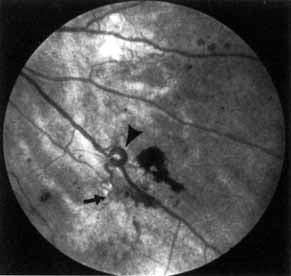

Although microaneurysms are the first ophthalmoscopically detectable change in diabetic retinopathy, the earliest abnormalities seen histopathologically are thickening of the capillary basement membrane1,2 and pericyte dropout.3,4 Pericytes are mesothelial cells that surround and support the retinal capillary endothelial cells. Normally there is one pericyte per endothelial cell. In people with diabetes, however, the pericytes die off and are decreased in number (Fig. 1). Their absence weakens the capillaries and permits thin-walled dilatations, called microaneurysms, to develop. Later, endothelial cells proliferate and lay down layers of basement membrane material. Fibrin may accumulate within the microaneurysm along with erythrocytes, and the lumen of the microaneurysm may become occluded (Fig. 2). Initially, most microaneurysms are on the venous side of the capillaries, but later they are seen on the arterial side as well. Clinically, they appear as small red dots (Fig. 3). Despite the multiple layers of basement membrane, microaneurysms are permeable to water and large molecules, allowing the transudation of fluid and lipid into the retina.

Fig. 1 A. Trypsin digest preparation of early background retinopathy. Normal retinal capillaries, with one pericyte (closed arrows) per endothelial cell (open arrows). B. Retinal capillary of a patient with diabetes with necrotic pericytes (arrows). (Courtesy of Dr. Myron Yanoff)

Fig. 3 A. Diabetic retinopathy with multiple microaneurysms, dot hemorrhages, and early neovascularization of the optic disc (NVD). A small blot hemorrhage is seen inferiorly. B. Continued. Midphase of the fluorescein angiogram. Patent microaneurysms are seen as hyperfluorescent dots. Note that most microaneurysms cannot be seen ophthalmoscopically. There is some enlargement of the foveal avascular zone because of some occluded capillaries. Temporally there is a larger zone of capillary nonperfusion. The NVD is beginning to leak. C. Late phase of the fluorescein angiogram showing diffuse leakage of fluorescein into the macula.

It is often difficult to distinguish a small dot hemorrhage from a microaneurysm by ophthalmoscopy alone. On fluorescein angiography patent microaneurysms will fill with dye quickly and then leak,5 unlike a small dot hemorrhage that will block fluorescence (see Fig. 3). However, angiography cannot distinguish a hemorrhage from a microaneurysm filled with clotted blood. Because fluorescein passes easily though them, we usually see many more microaneurysms on fluorescein angiography than are apparent on examination.6

When the wall of a capillary or microaneurysm is thin, it may rupture, giving rise to an intraretinal hemorrhage. If the hemorrhage is deep (i.e., in the inner nuclear layer or outer plexiform layer), it usually has a round or oval shape (“dot or blot”) (see Fig. 3). Superficial (nerve fiber layer) hemorrhages, on the other hand, become flame- or splinter-shaped indistinguishable from that seen in hypertensive retinopathy. Although people with diabetes with normal blood pressure may have multiple splinter hemorrhages, they should nevertheless have their blood pressure checked because a frequent complication of diabetes is systemic hypertension.